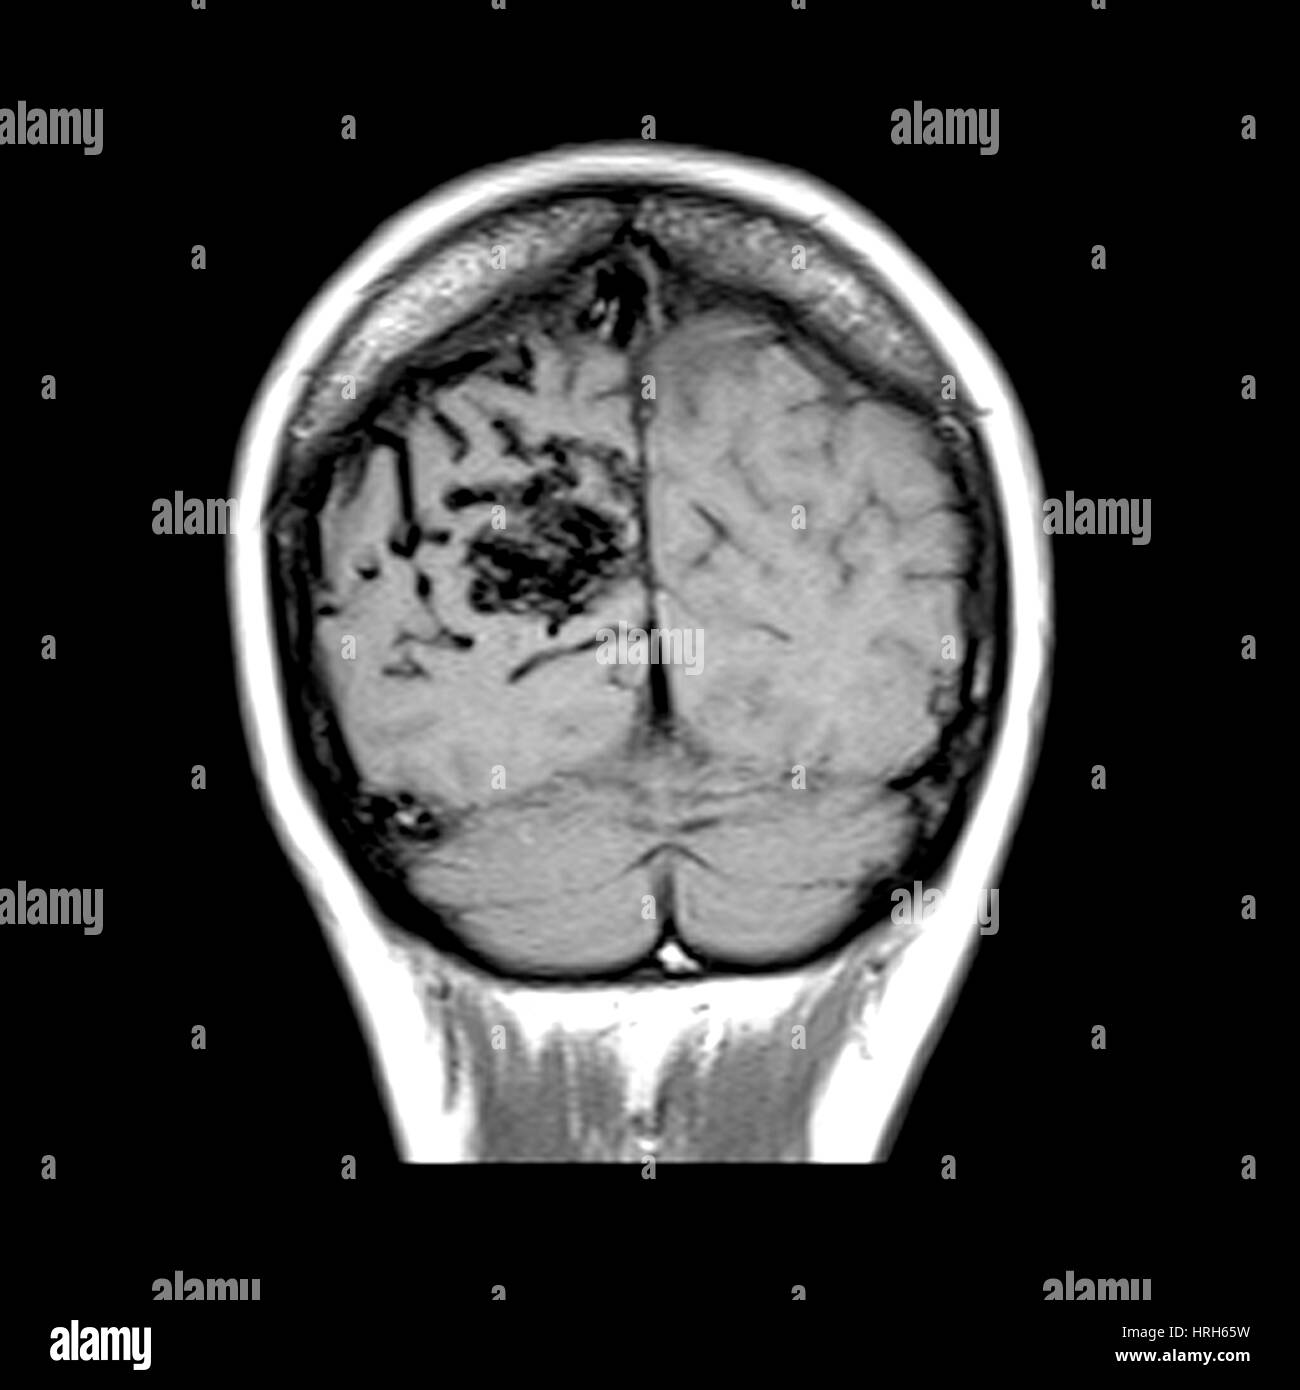

MRI of Arterial Venous Malformation Stock Photo Alamy What Is A Venous Mri Chronic venous insufficiency (cvi) is a form of venous disease that occurs when. Magnetic and radio waves create detailed 3d images of your blood vessels and brain. The thrombus vs slow flow. The veins drain into a larger central vein. A diagnostic procedure that uses a combination of a large magnet, radiofrequencies, and a computer to produce detailed images of. What Is A Venous Mri.

From www.alamy.com